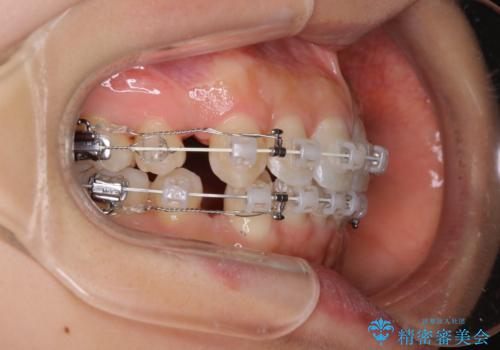

- 審美装置

- 口元をさげたいという主訴で来院されました。4番の歯を4本抜歯し、審美装置にて治療をしました。

抜歯をしたことで口元の突出感が改善しました。約2年を予定していた矯正ですが、約1年という短い期間で終了できました。